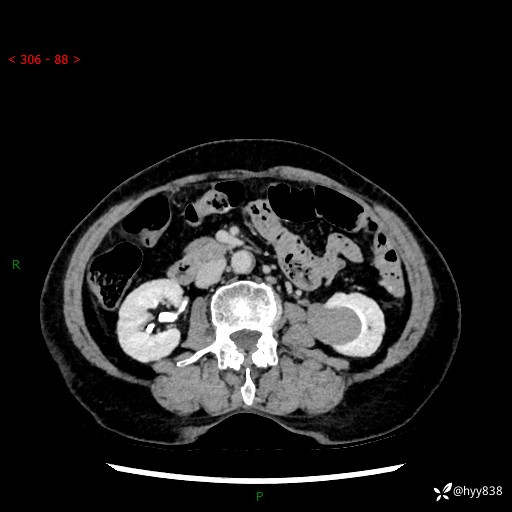

72岁/女,检查发现左肾占位1天。为了满足诊断,常规四期后,又加了延迟期-结果公布~

【患者信息】:72岁/女

【主诉】:检查发现左肾占位1天

【现病史及既往史】:患者于1天前检查发现左肾占位,无畏寒发热,无咳嗽咳痰,无腰腹部疼痛不适,无肉眼血尿、无尿频尿急症状,起病来,患者未行特殊治疗,为求进一步诊治,门诊以"左肾占位"收治入院。 发病来患者精神、饮食、睡眠良好,小便如上,大便正常,体重无明显变化。

【检查】:肾脏CT平扫+增强